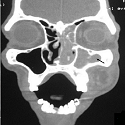

Tuméfaction nasogénienne: ne pas oublier un kyste nasolabial

Moncef Sellami, Abdelmonem Ghorbel

PAMJ. 2017; 26: 202. Published 13 April 2017